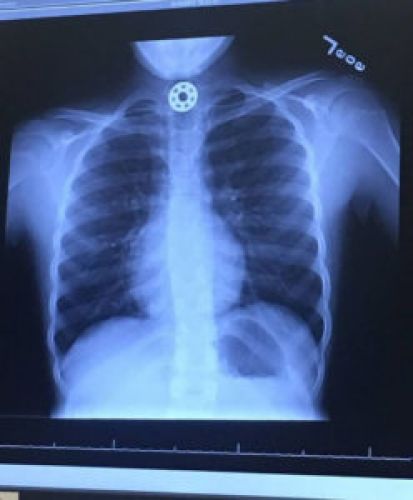

En una carrera contrarreloj por salvar la vida de su hija, Kelly se presentó directamente en el hospital, donde los médicos no pudieron localizar qué estaba causando la asfixia ni dónde se encontraba hasta que la radiografía lo mostró con claridad: una de las tres ruletas metálicas del juguete estaba atascada en el esófago de la niña. “El médico estaba fascinado… esa misma mañana había conocido los spinners cuando estaba en el centro comercial con su hijo, por lo que fue una sorpresa para él enfrentarse con uno en un caso de estas características“, contaba incrédulamente Kelly.